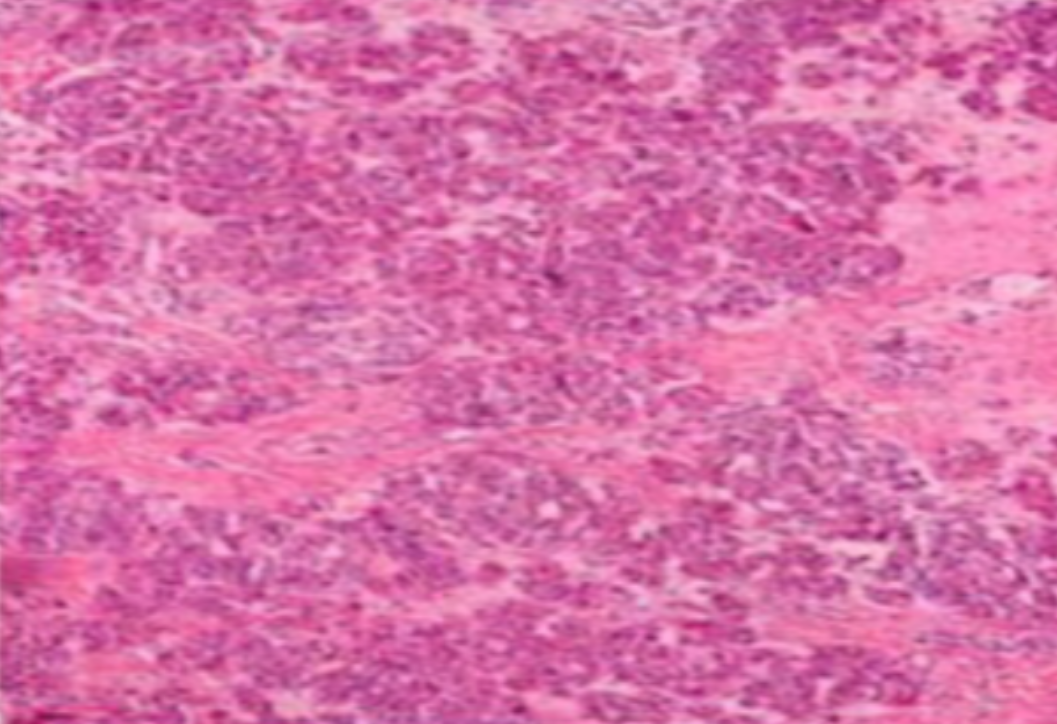

虽然HE染色是最常见且最基础的染色技术之一,😭但在实验过程中,很容易出现各种情况导致染色切片质量参差不齐。所以,小编根据以往实验经验,给大家整理归纳出了15个HE染色中的常见问题,还包含问题原因分析以及解决方法哦~

形成原因:切片经梯度乙醇处理后没有完全脱水,导致二甲苯透明、中性树胶封固后残留大量水分。 解决方法:首先移去盖玻片,用二甲苯溶解封固剂如中性树胶,再将切片置入无水乙醇内,待切片重新脱水完全后,用二甲苯透明处理,中性树胶封固。要注意所有用于脱水和透明的液体,在使用一定时间后,应及时更换。 二、细胞核呈红、棕色 形成原因:苏木精染色液过度氧化,切片在苏木精染液染色后返蓝不足。 解决方法:每次染色之前检查苏木精染色液的染色能力,发现苏木精染色液氧化过度应及时更换。此外,切片经苏木精染色后,要给切片以足够的蓝化时间,蓝化过程可用流水、温水、弱碱性溶液(如稀氨水或0.2%碳酸氢钠)等处理。 三、切片在脱蜡后出现大片白色斑点 形成原因:由于烤(烘)片温度太低,切片上的组织蜡膜在脱蜡前没有充分烤(烘)融化。或是因为切片在二甲苯液中停留时间不足,或二甲苯使用过久,造成的脱蜡不彻底。 解决方法:若是由于切片烤(烘)温度低所致,可以先用二甲苯去除切片上的封固胶,然后重新用二甲苯脱去切片上的石蜡,再进行后续染色。若是由于切片在脱蜡的二甲苯中停留时间不足或脱蜡二甲苯使用过久浓度不足所致,则需将切片退回到二甲苯中,停留较长时间,或更换二甲苯液体重新脱蜡,再入乙醇重新脱二甲苯,入0.5%盐酸水溶液褪色后,重新HE染色。 四、细胞核苍白暗淡,即苏木精染色太淡 形成原因:切片在苏木精染色液停留时间太短;苏木精染色液过度氧化,失去染色能力,不能再继续使用;分化步骤处理时间过长;固定不及时。此外值得注意的是,若骨组织细胞核暗淡,大多是脱钙过度造成的。 解决方法:切片重新染色。如果组织在酸性固定液(如Zenker、Bouin)或非中性缓冲甲醛液固定时间过长,细胞核染色能力将减弱,需增加其在苏木精染色液的时间,或用一些方法增加组织的嗜碱性,以改善细胞核的着色。例如,上述组织玻片可以使用Weigert铁苏木精染色液。如果组织是用Zenker液固定的,可将切片脱蜡后放在5%碳酸氢钠溶液3~4h,流水冲洗5min后染色。如果组织是用Bouin液固定的,可将切片脱蜡后放在5%碳酸锂1h,流水冲洗10min后染色。 五、细胞核过染,苏木精染液占据了细胞质 形成原因:玻片在苏木精染色液停留时间过长,或是切片太厚、分化步骤时间太短。 解决方法:如果不是因为切片太厚(用显微镜仔细上下微调,只有一二层细胞核层次),就需将切片进行脱色、漂白、重新染色,适当调整染色和分化时间。但如果确定是由于切片太厚导致的细胞核过染,则需要重新切片。 六、伊红着色淡 形成原因:可能是伊红染液pH值大于5,也可能是蓝化液残留过多,切片太薄,或是切片经伊红染色后在乙醇脱水时间过长。 解决方法:检查伊红染液pH值,必要的话,用乙酸将其调节在4.6~5.0之间,从而使伊红染色色彩艳丽。此外,确保每次蓝化步骤完成后,使用的弱碱性溶液被充分洗去,玻片上没有残留的弱碱性溶液。最后,检查切片的厚度,且脱水时不要让切片在低浓度乙醇中停留时间过长,因为含水多的低浓度乙醇会将切片伊红的颜色分化掉。 七、细胞质过染、分色不足 形成原因:伊红染色液浓度太高,特别是存在焰红燃料、四溴四氯荧光素钠。切片在伊红染色时间过长,或是切片在伊红染色后经乙醇脱水步骤时时间太短,而使乙醇分化伊红的作用不能产生,都能够使细胞质过染。 解决方法:适当稀释伊红染色液,减少伊红染色时间,或使切片在乙醇脱水等步骤时,停留时间相对均匀。同样,也要检查切片的厚度是否合适。 八、切片中出现蓝黑色沉淀物 形成原因:苏木精染色液中的金属膜黏附在玻片上。 解决方法:染色前仔细过滤苏木精染色液,建议使用半氧化苏木精染色液,如Gill苏木精染色液,可以避免过多的金属膜产生。 九、光镜下切片某些区域难以聚焦 形成原因:盖玻片上可能有封固切片的封固剂。 解决方法:移去盖玻片,重新用干净的盖玻片封片。检查切片封片方法,是人工手工封法,还是机器自动封法,如有问题及时调整。 十、封固剂从盖玻片与载玻片之间的缝隙回缩 形成原因:盖玻片弯曲或不平整,或是封固剂含二甲苯过多,稀释过度。 解决方法:移去盖玻片,重新找一张盖玻片,用干净的封固剂封片。如用手工封片法,保证在封固结束时,封固剂容器盖子为紧闭状态。且尽量使用小的容器盛装封固剂,一旦封固剂太黏稠,就可以选择废弃。 十一、细胞核呈灰蓝状态 形成原因:可能由于组织处理温度过高、过热,在液体石蜡中停留的时间过长。或是固定时间太短后,直接在高浓度的乙醇中进行了脱水处理。 解决方法:理论上来说,仅在组织浸蜡步骤才进行加热,组织不能在热蜡液中停留太久。如果由于某些原因不能进行下一步包埋处理,可将组织连同塑料包埋盒一并放置在室温空气中,冷却凝固,以备包埋。待需要包埋时再重新加温直至石蜡融化即可。组织在处理前必须确保固定良好,脱水最好能从低浓度的乙醇开始。 十二、类色素的点状结晶和黑色光滑细胞核 形成原因:这种裸核改变是因为切片封片前放置在空气中的时间太长,以至于二甲苯挥发,切片干燥。 解决方法:移去组织切片上的盖玻片和封固剂,重新处理。将切片水洗数分钟,然后重新脱水、透明、封固。封片过程中要保持组织切片的轻度湿润,尽量不要让其干燥。 十三、染色过淡或过浓 解决方法:如果染色过淡,可以增加染色剂的浓度、延长染色时间或更换新鲜的染色剂;如果染色过浓,则应减少染色剂的浓度或缩短染色时间。 十四、切片出现叠加褶皱 形成原因:新购买的玻片洁净度不够、用镊子撑开切片时操作不够熟练未能平整伸展,或玻片表面有油脂,切片粘贴不牢。另外,烤片时间不足、烤片温度过低或切片过厚造成切片脱落,都会造成重叠或有皱褶的情况。 解决方法:新购买的玻片最好能用硫酸清洁液浸泡一晚,然后流水冲洗干净。在适宜的温度下烤片时间宁长勿短,保证有充足的烤片时间和温度。另外,切片刀要锋利,才能切出厚薄适宜的切片,保证切片不会因为过厚而脱落。 十五、组织残缺不全或有刮划痕迹 形成原因:组织残缺不全是由于切片时修整蜡块时深度不够、组织没有全部暴露于切面。切片的刮划痕迹是由于切片刀的刀锋有缺口、包埋的组织有异物,或是钙化组织、骨组织及包埋石蜡有沙粒造成的。 解决方法:修整蜡块时保证组织块全部暴露于切面,切片时保证切片刀的锋利没刀口。同时在组织取材时去除手术异物和钙化组织。最后,骨组织要完全脱钙,这样可以保证切片的完整和平整美观。 *注:由于实验中导致结果出现误差的原因多种多样,以上内容仅供参考,具体根据实际情况进行判断。